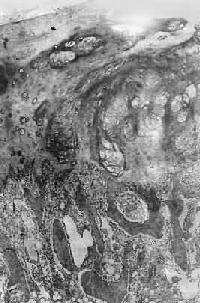

图17-6 骨巨细胞瘤(Ⅰ级)

肿瘤由大量基质细胞和多核巨细胞两种细胞组成